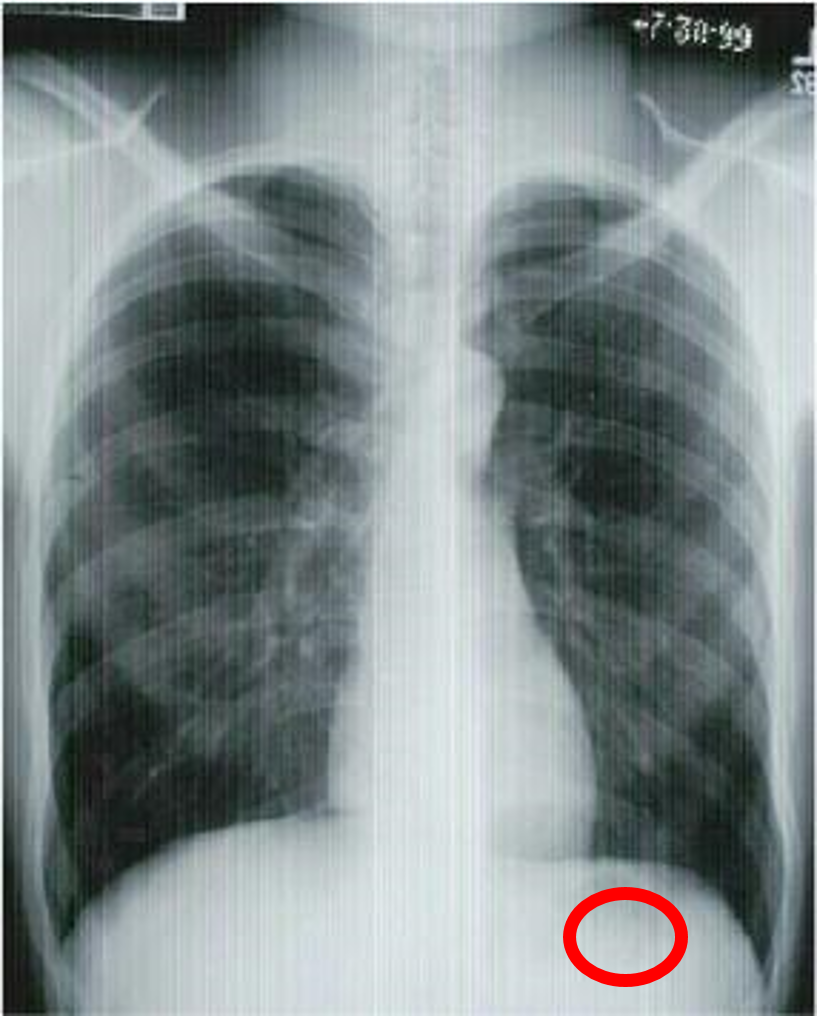

what view is this?

give three indicators

PA chest

aortic arch

diaphragm

left ventricle

liver

pulmonary artery

right atrium

right mainstem bronchus

stomach

trachea